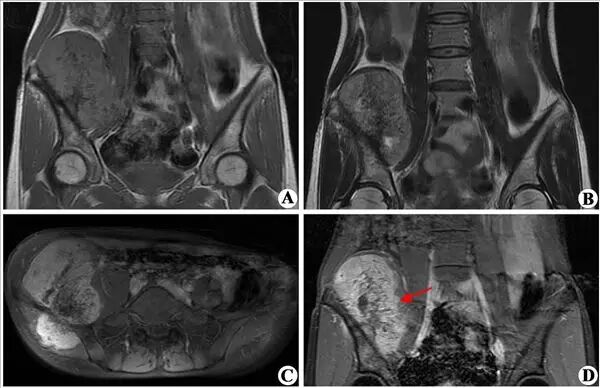

右侧髂骨软骨肉瘤。右侧髂骨信号异常。T2WI(B)显示右侧髂骨骨质破坏,其内上方见椭圆形肿块,为不均匀等信号,中间散在点、条状低信号;T1WI(A)肿块为不均匀低信号,增强扫描(C、D)肿块明显不均匀强化。